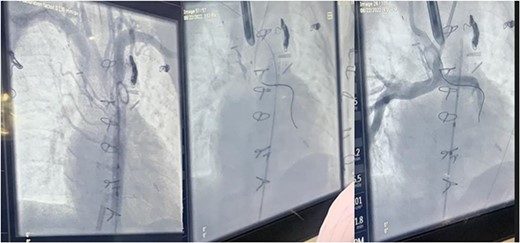

During the procedure in the catheter lab, our team placed a 5 mm balloon over a 3.5 mm bronchoscope, shown in Fig. 1, through the suction port and advanced to the level of the carina. Utilizing fluoroscopy, the balloon was advanced to the narrowed portion of the left main stem bronchus. After this placement was confirmed, the interventional cardiology team tunneled their balloons into the left pulmonary artery and aorta. Markers on the balloons were utilized to ensure the airway and intravascular balloons were adjacent. At this time, both intravascular balloons and the bronchial balloon were simultaneously inflated under direct fluoroscopic visualization, shown in Fig. 2. The bronchial balloon was deflated and removed at this time. The left mainstem bronchus was then visualized, whereas the intravascular dilation and stent placement occurred. During this step of the procedure, the left mainstem bronchus appeared wider compared with its preoperative state and no narrowing of the bronchus was observed upon additional intravascular balloon dilation. The patient improved dramatically within the postoperative period, however needed a further cardiac catheterization to dilate his aortic and pulmonary artery stent. Pediatric otolaryngology was again involved to inflate a balloon to prevent further bronchial compression. Once appropriately prepped, we introduced a 3 mm bronchoscope to the left main bronchus. Under direction of the interventional cardiologist, the balloon introduced into the left mainstem bronchus was visualized under fluoroscopy, advanced to the appropriate position determined by the interventional cardiologist, and then inflated. The balloon size was 6 mm in diameter and 20 mm in length and it was inflated to atmospheric pressure and kept inflated while the interventional cardiologist performed their balloon dilation of left pulmonary artery along with a stent placed in the left pulmonary artery and aorta. The balloon was then deflated and withdrawn and the resultant bronchus was larger in comparison to pre-op. The patient tolerated the operation well.

Fluoroscopic intraoperative images of left mainstem bronchus balloon dilation.